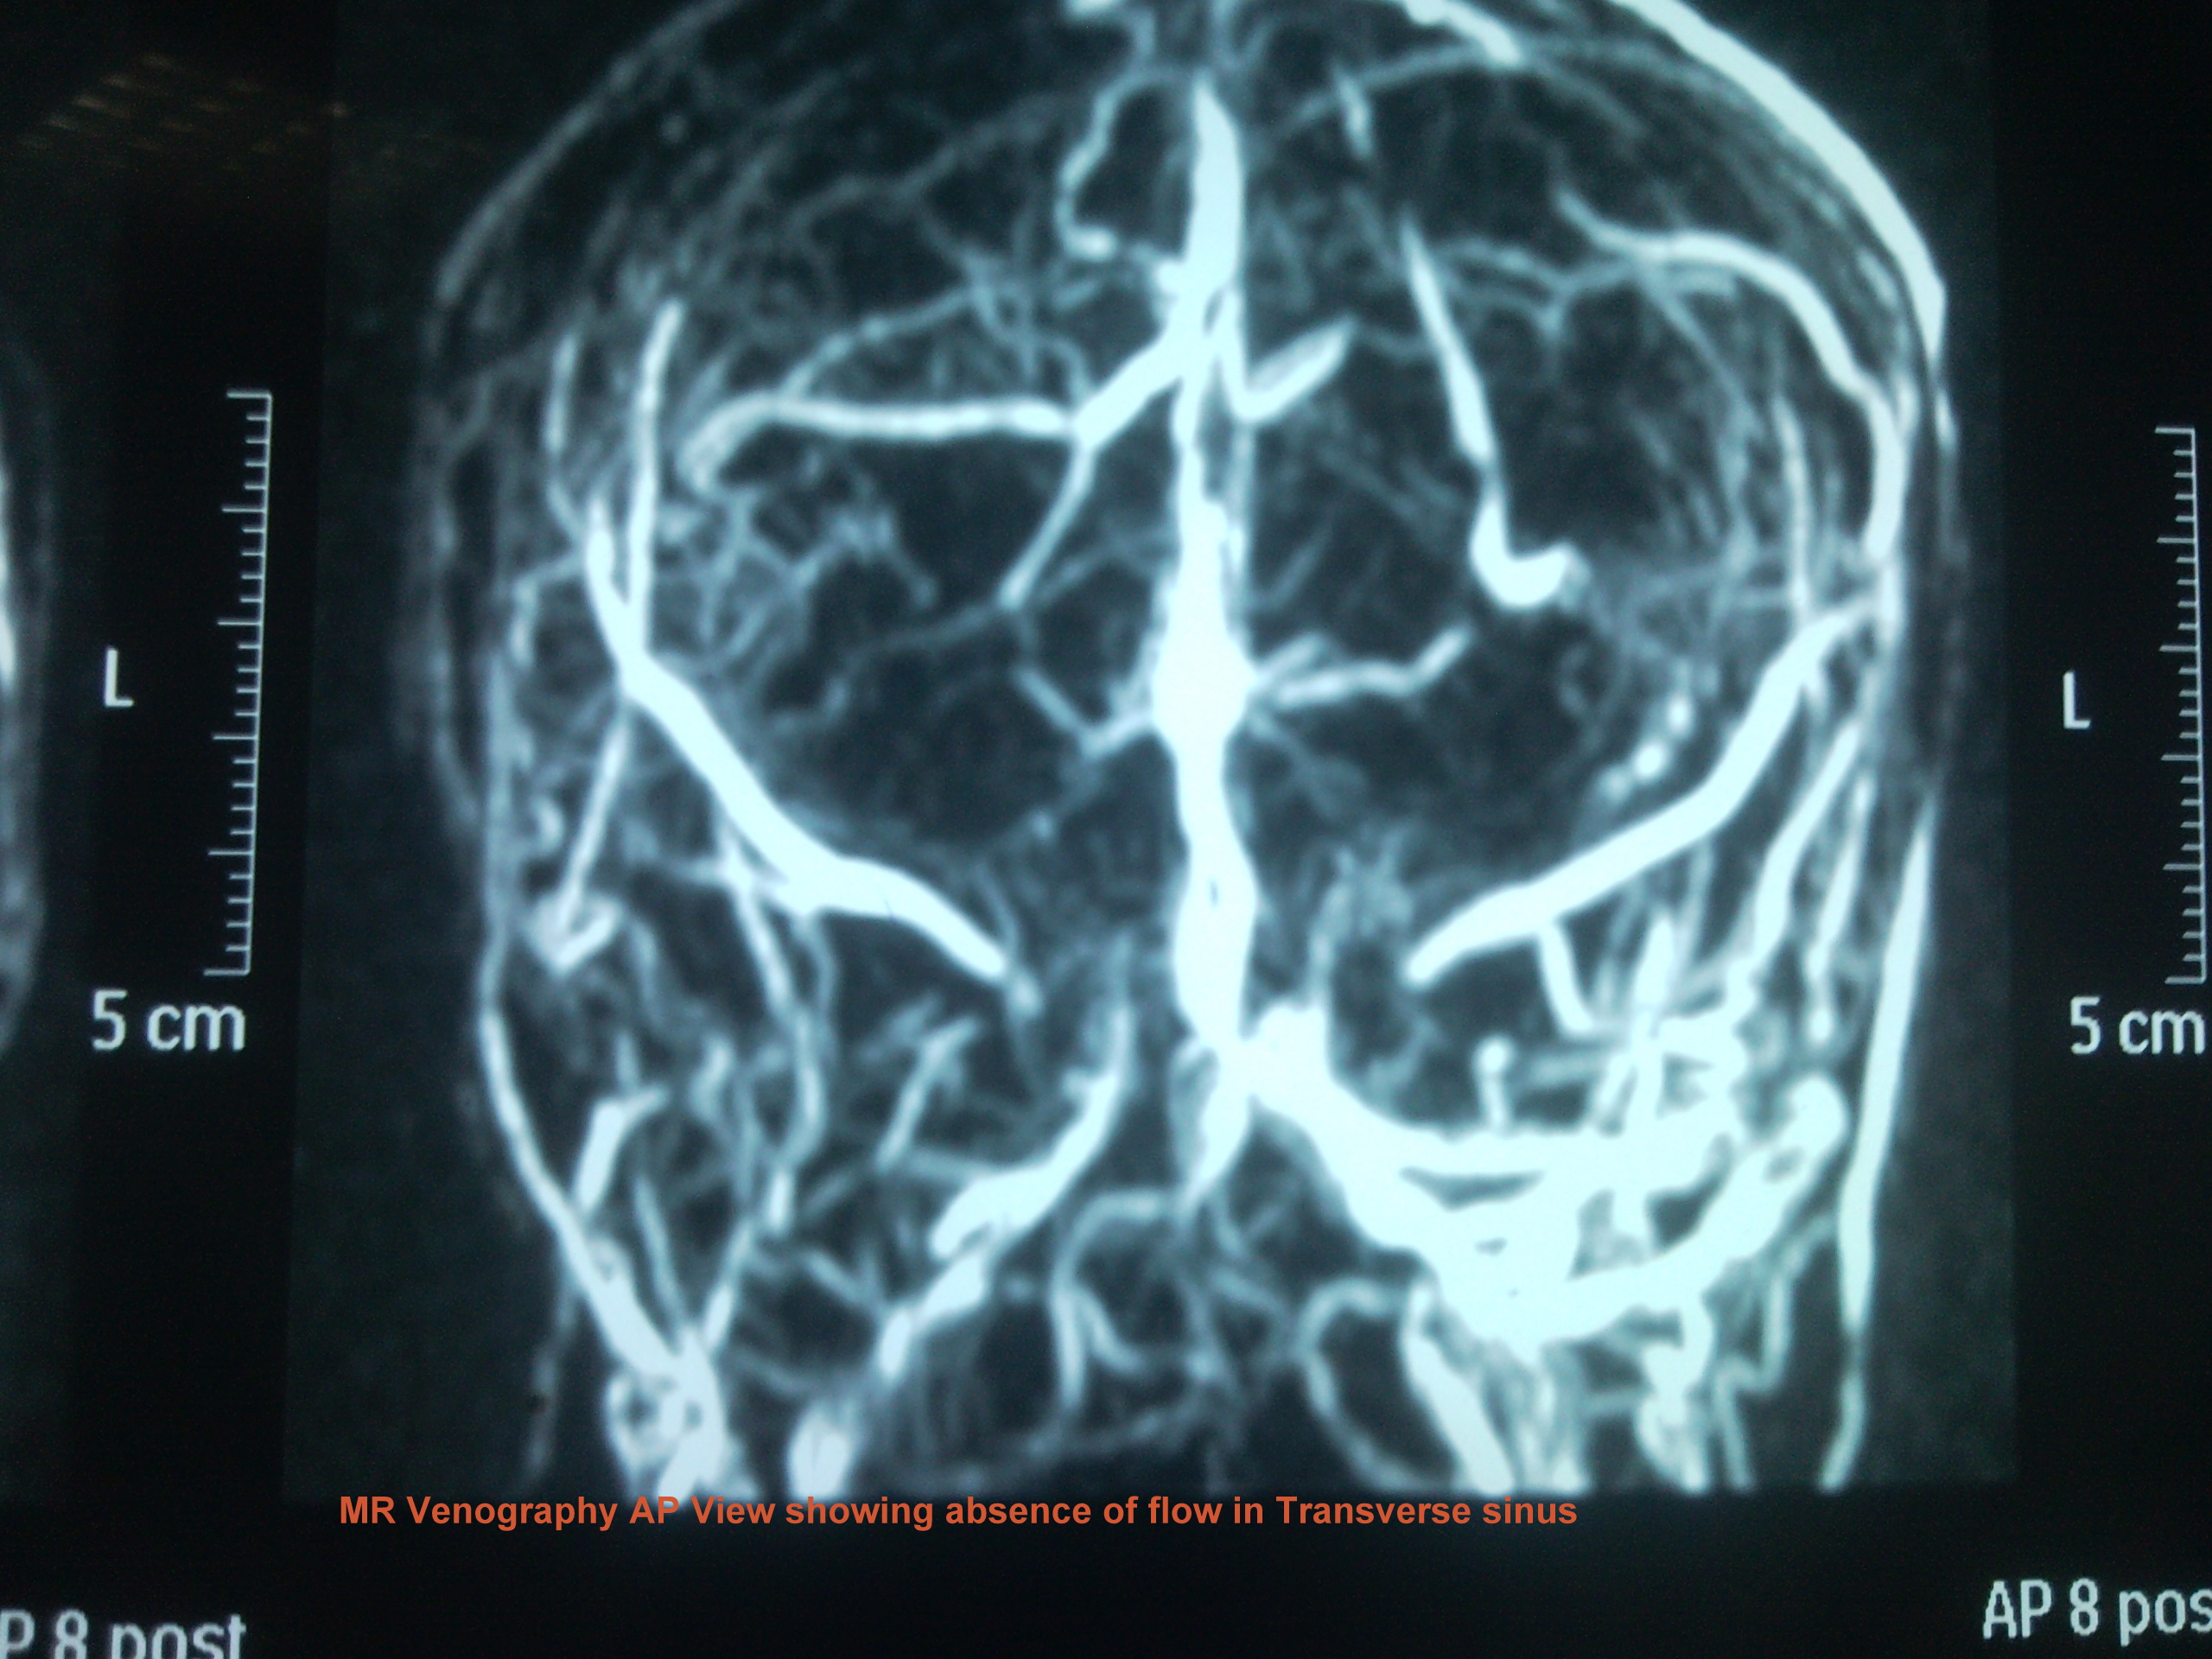

We present a case of 29 years old female patient with 20 days history of headache, projectile vomiting and low grade fever. She was referred from Swat where she was locally treated as acute pyogenic meningitis with no improvement. Patient had right 6th cranial nerve palsy and papilledema. CT brain was unremarkable and MRI brain with MR Venography showed superior sagital, confluence of sinuses and transverse sinus thrombosis.